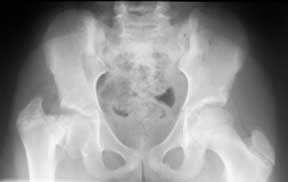

An X-ray of the hips showing a normal left side and coxa vara on the right side.

The Cincinnati Children's Hip Preservation Program treats patients with coxa vara. Coxa vara is an unusual hip condition in which there is a discrepancy of growth in the round ball of the hip (femoral head) and the upper end of the thigh bone. This discrepancy leads to a shepherd's crook deformity of the hip.

Coxa vara usually presents with a limp, a leg length difference, and limited ability to bring the thigh out to the side. X-rays are used to diagnose coxa vara.